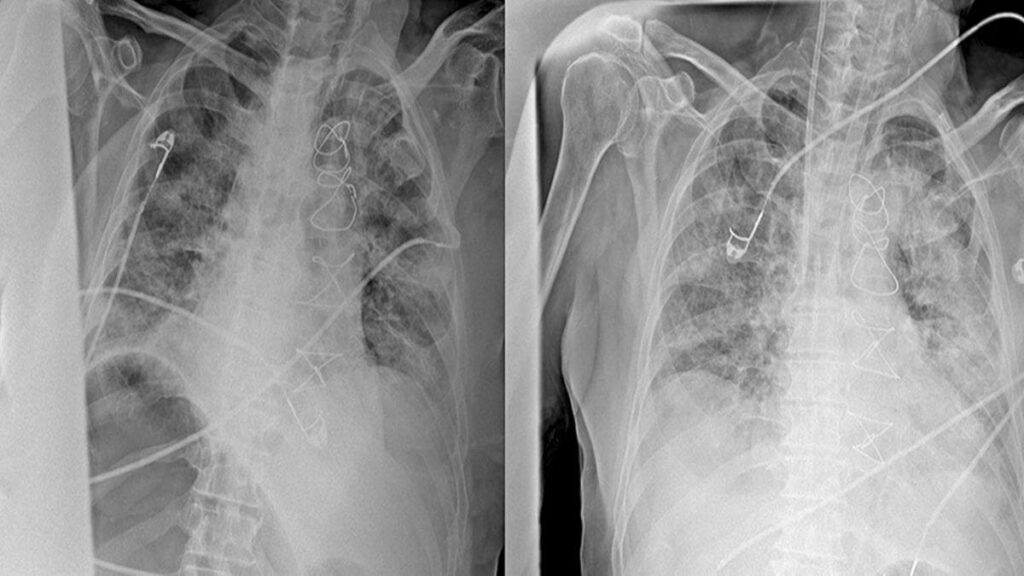

Hangi Testler Ve Muayene Yaklaşımı Öne Çıkar?

Uzman değerlendirmesinde şikâyet süresi, maruziyet öyküsü ve muayene bulguları önemlidir. Gerekli görüldüğünde akciğer filmi, solunum fonksiyon testi veya ileri görüntüleme gibi yöntemler kullanılabilir.